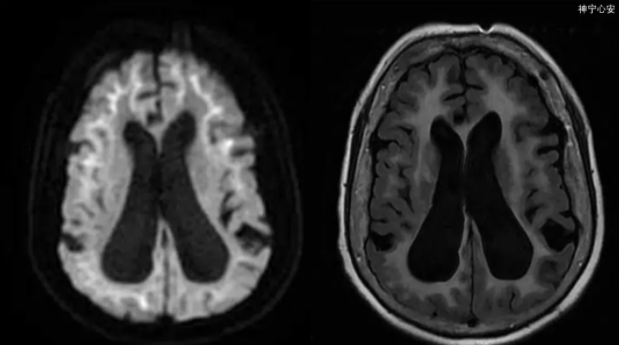

发病率仅次于阿尔茨海默病!一次中风,变得判若两人......

2023-07-04

七旬老太记忆不好竟不是老年痴呆!杭七院MDT团队剥丝抽茧最终确诊罕见病

2023-06-13